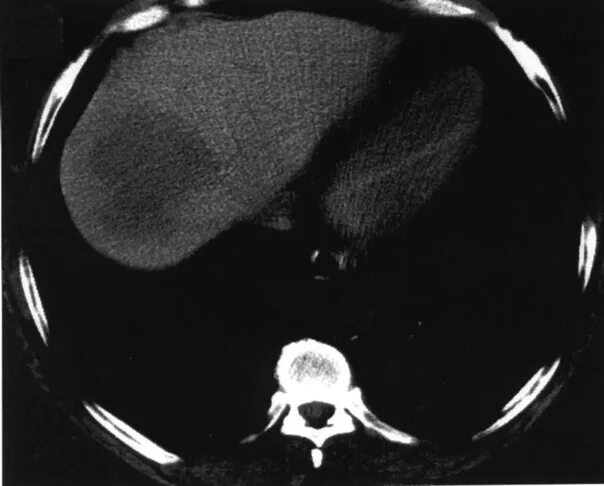

Гиподенсивное образование что это значит